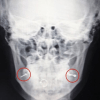

20 января 2021В Люберцах врачи экстренно прооперировали пациентку с неправильным пирсингомВрачи Люберецкой областной больницы провели пациентке операцию по удалению пирсинга с пластикой местными тканями, сейчас девушка выписана под амбулаторное наблюдение врача стоматолога-хирурга, сообщили в медучреждении. ⠀